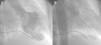

Case reportA 73-year-old woman was admitted to our coronary care unit complaining of typical chest pain at rest that developed two hours before, after she was informed of her brother's death. Six years before, a VVIR pacemaker was implanted due to sick sinus syndrome with occasional bursts of atrial fibrillation. On admission, myocardial necrosis markers were elevated, with first troponin I measurement of 0.46 IU/ml, with a peak of 0.75 IU/ml (normal <0.2 IU/ml) 11 hours after pain onset. Creatine kinase remained within normal limits. A transthoracic echocardiogram showed left ventricular ejection fraction (LVEF) of 37% with apical akinesia. A previous control echocardiogram, one month before, was available showing no wall motion abnormalities and normal LVEF (70%). Cardiac catheterization was performed three days later, showing normal coronary arteries and severe apical hypokinesia (Figure 1). In-hospital stay was seven days. Full recovery of left ventricular wall motion was observed on an echocardiogram performed 51 days after the onset of symptoms. During a follow-up of 24 months, the patient remained free of symptoms of ischemic cardiomyopathy and the echocardiogram was unchanged.